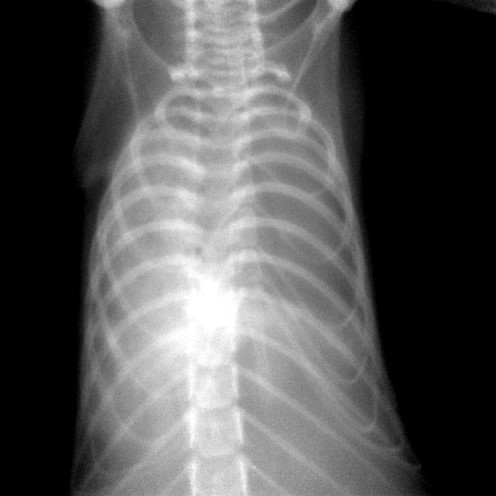

The PAM mouse model study was inspired by a patient seen by Dr. McCormack in 2011 at UC Medical Center. The woman had been diagnosed with PAM as a child in Jordan and developed exertional dyspnea at the age of 54, a typical pattern for PAM. Chest examination revealed bibasilar crackles, pulmonary function tests revealed mild restriction and reduced diffusing capacity, and a six-minute-walk test revealed normal exercise capacity with mild exertional desaturation to 88%.1 Chest X-ray showed fine hyper dense lower lung zone nodular opacities, and computed tomography of the chest showed symmetrical lower lobe predominant micronodular calcifications along bronchovascular bundles and interlobular septal thickening, findings pathognomonic for PAM.1

Chest x-ray of patient with PAM showing hyper dense, fine nodular opacities in the lower lung zones1.